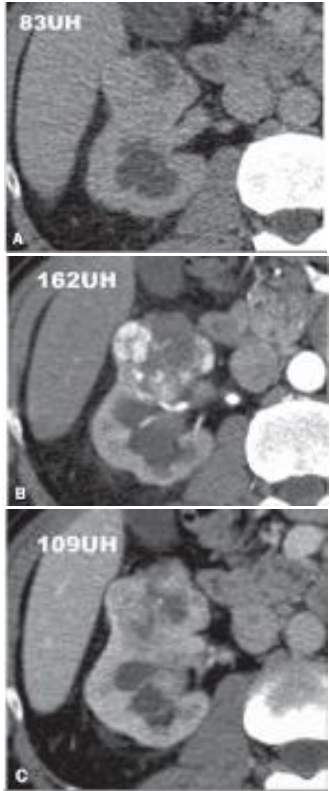

A TC a seguir é um exemplo de carcinoma de células renais.

Em relação à classificação histológica do carcinoma de células renais (CCR) e sua correlação com os métodos de imagem, assinale a afirmativa correta.